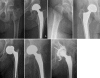

Background: Femoral neck fractures in the elderly are frequent, represent a great health care problem, and have a significant impact on health insurance costs. Reconstruction options using hip arthroplasty include unipolar or bipolar hemiarthroplasty (HA), and total hip arthroplasty (THA). The purpose of this review is to discuss the indications, limitations, and pitfalls of each of these techniques.

Results: THA yields the best functional results in patients with displaced femoral neck fractures with complication rates comparable to HA. THA is beneficially implanted using an anterior approach exploiting the internervous plane between the tensor fasciae latae and the sartorius muscles allowing for immediate full weight-bearing. Based on our findings, bipolar hemiarthroplasty, similar to unipolar hemiarthroplasty, cannot restorate neither anatomical nor biomechanical features of the hip joint. Therefore, it can only be recommended as a second line of defense-procedure for patients with low functional demands and limited live expectancy.

Conclusions: THA is the treatment of choice for femoral neck fractures in patients older than 60 years. HA should only be implanted in patients with limited life expectancy.